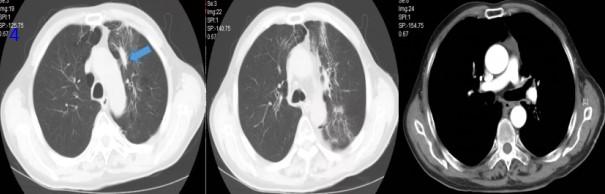

2020年12月29日,放療后1個月復(fù)查胸部CT可見腫瘤及轉(zhuǎn)移淋巴結(jié)較前縮?。▓D3),RECIST評價,PR。

圖3 放療后1月胸部CT

2021年3月19日,放療后3個月,因胸悶、憋喘復(fù)查胸部CT可見雙肺炎性病變,腫瘤繼續(xù)縮小(圖4),考慮放射性肺炎給與甲潑尼龍對癥治療好轉(zhuǎn)。

圖4 放療后3個月胸部CT